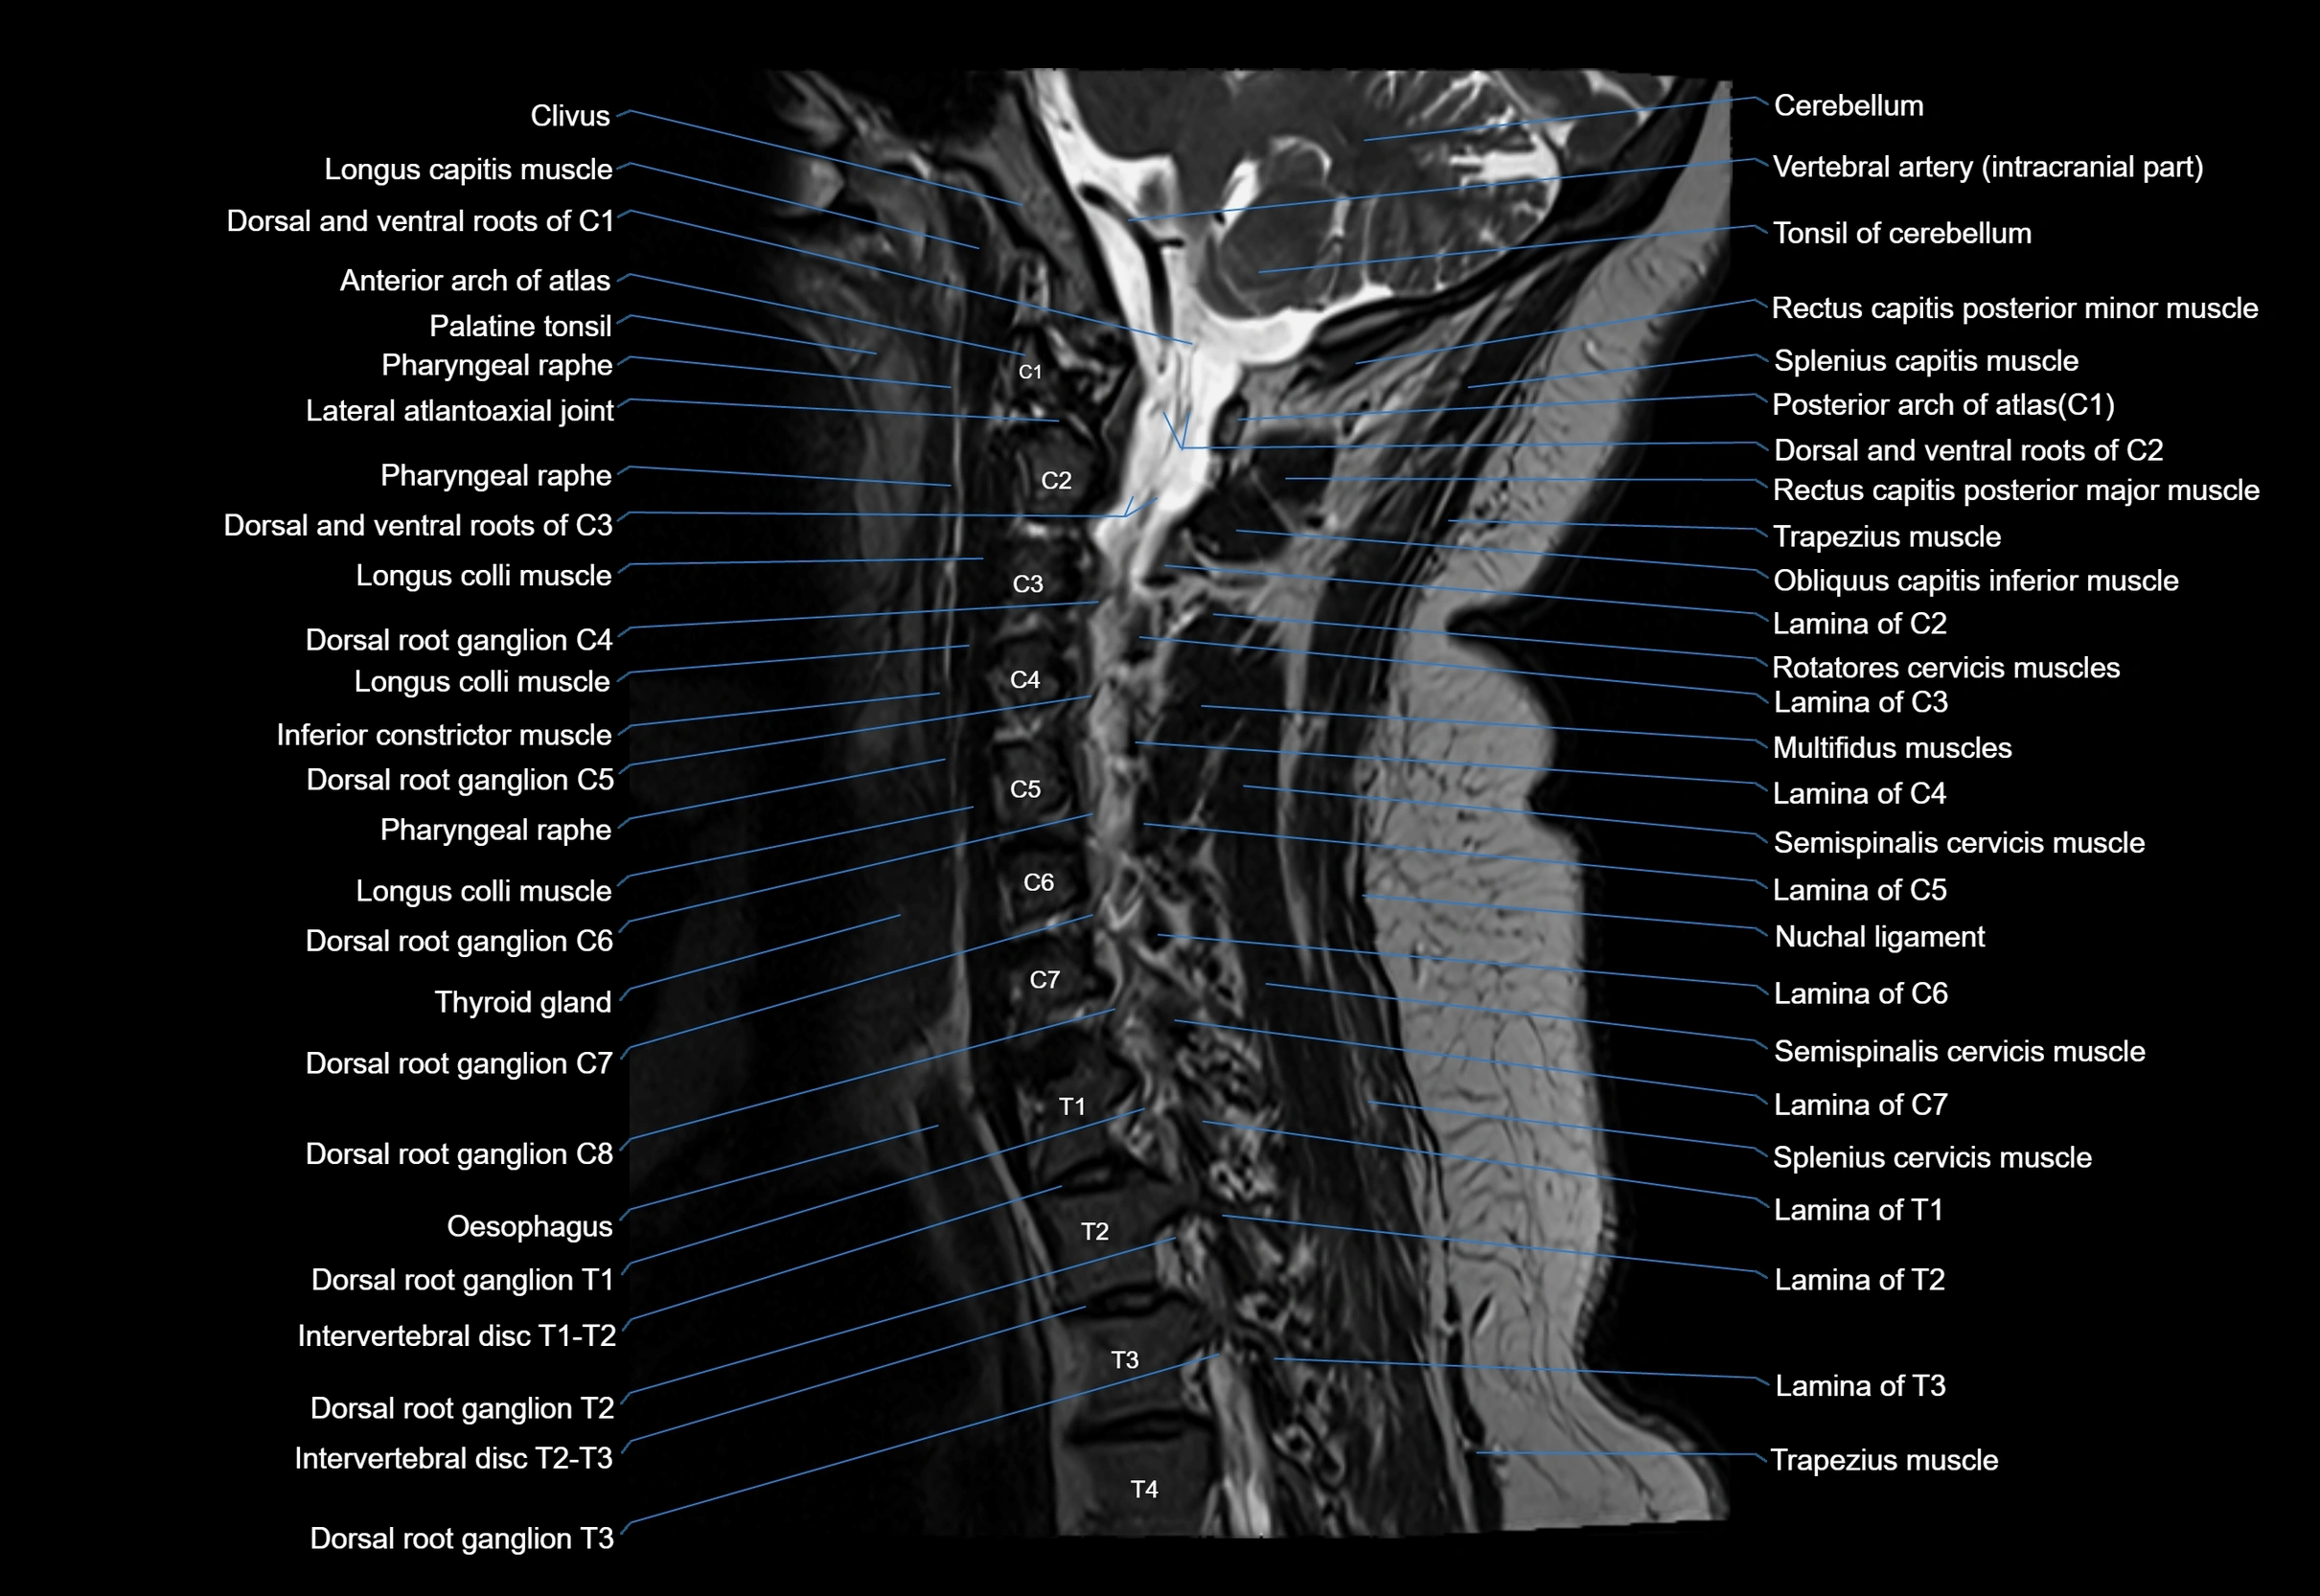

MRI image

image